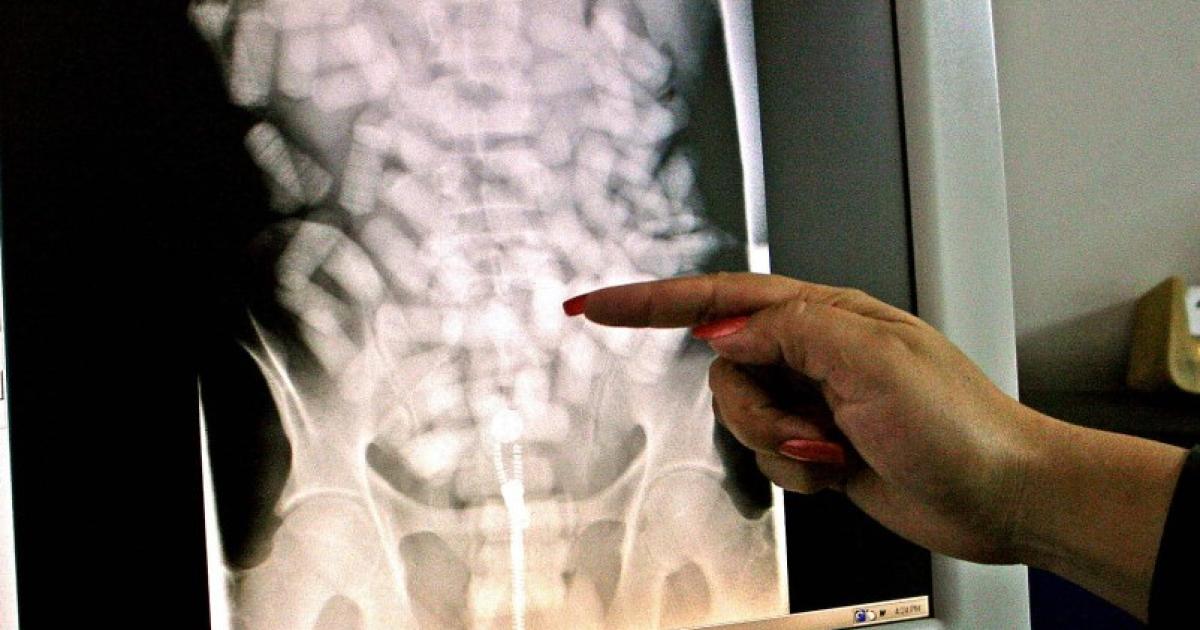

La radiographie effectuée au CHU par la suite, a révélé une quantité impressionnante d’ovules dans son corps, des petites tâches rondes, allant du bassin jusqu’au haut de l’abdomen. Environ 200 au total, pour un poids estimé à 1,6kg.